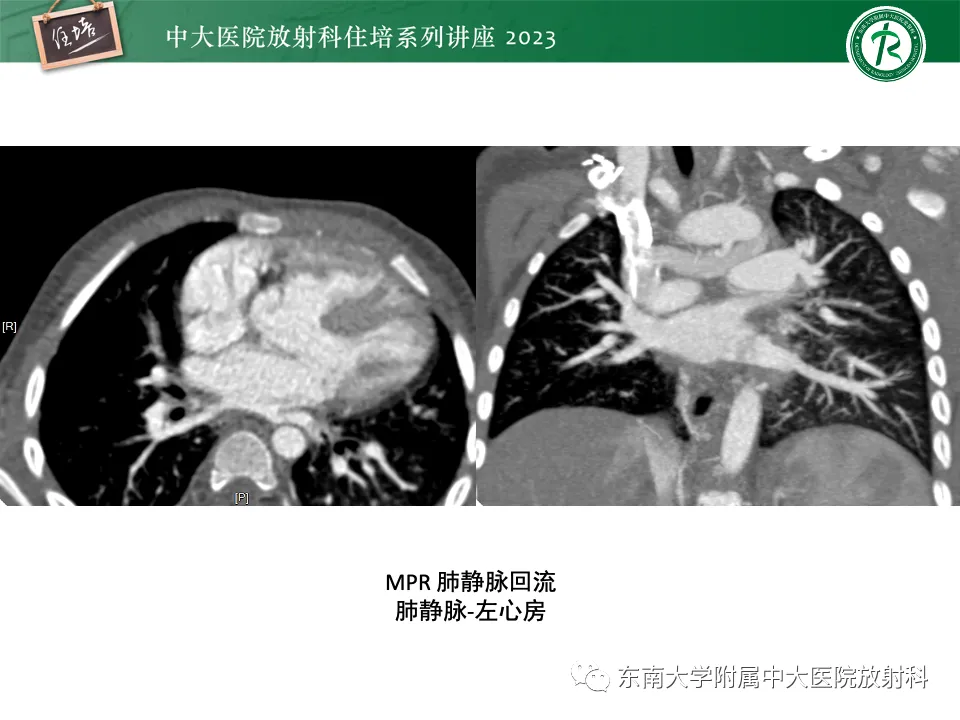

>精美课件丨心脏大血管常见疾病CT图像后处理要点

精美课件丨心脏大血管常见疾病CT图像后处理要点

来源:东南大学附属中大医院医学影像科